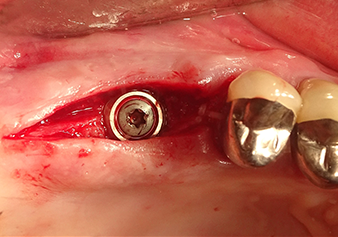

Implant bed preparation and augmentation

Following an intermediate check (Fig. 4) a further preparation step was performed (Fig. 5). Afterwards, the hydraulic Z35P instrument was used to lift the membrane to the desired position (Fig. 6 and 7). This was followed by further piezosurgical preparation of the implant bed, concluded with a rotary bur and shoulder milling cutter up to the implant diameter of 4.8 mm. Before the implant was inserted, the augmentation material (particle size approx. 0.8-1.6 mm) was introduced underneath the Schneiderian membrane (Fig. 8).

Situation after insertion of the implant

Fig.9: Situation after insertion of the implant (length: 10 mm, prosthetic platform: 6.5 mm) immediately before suturing.